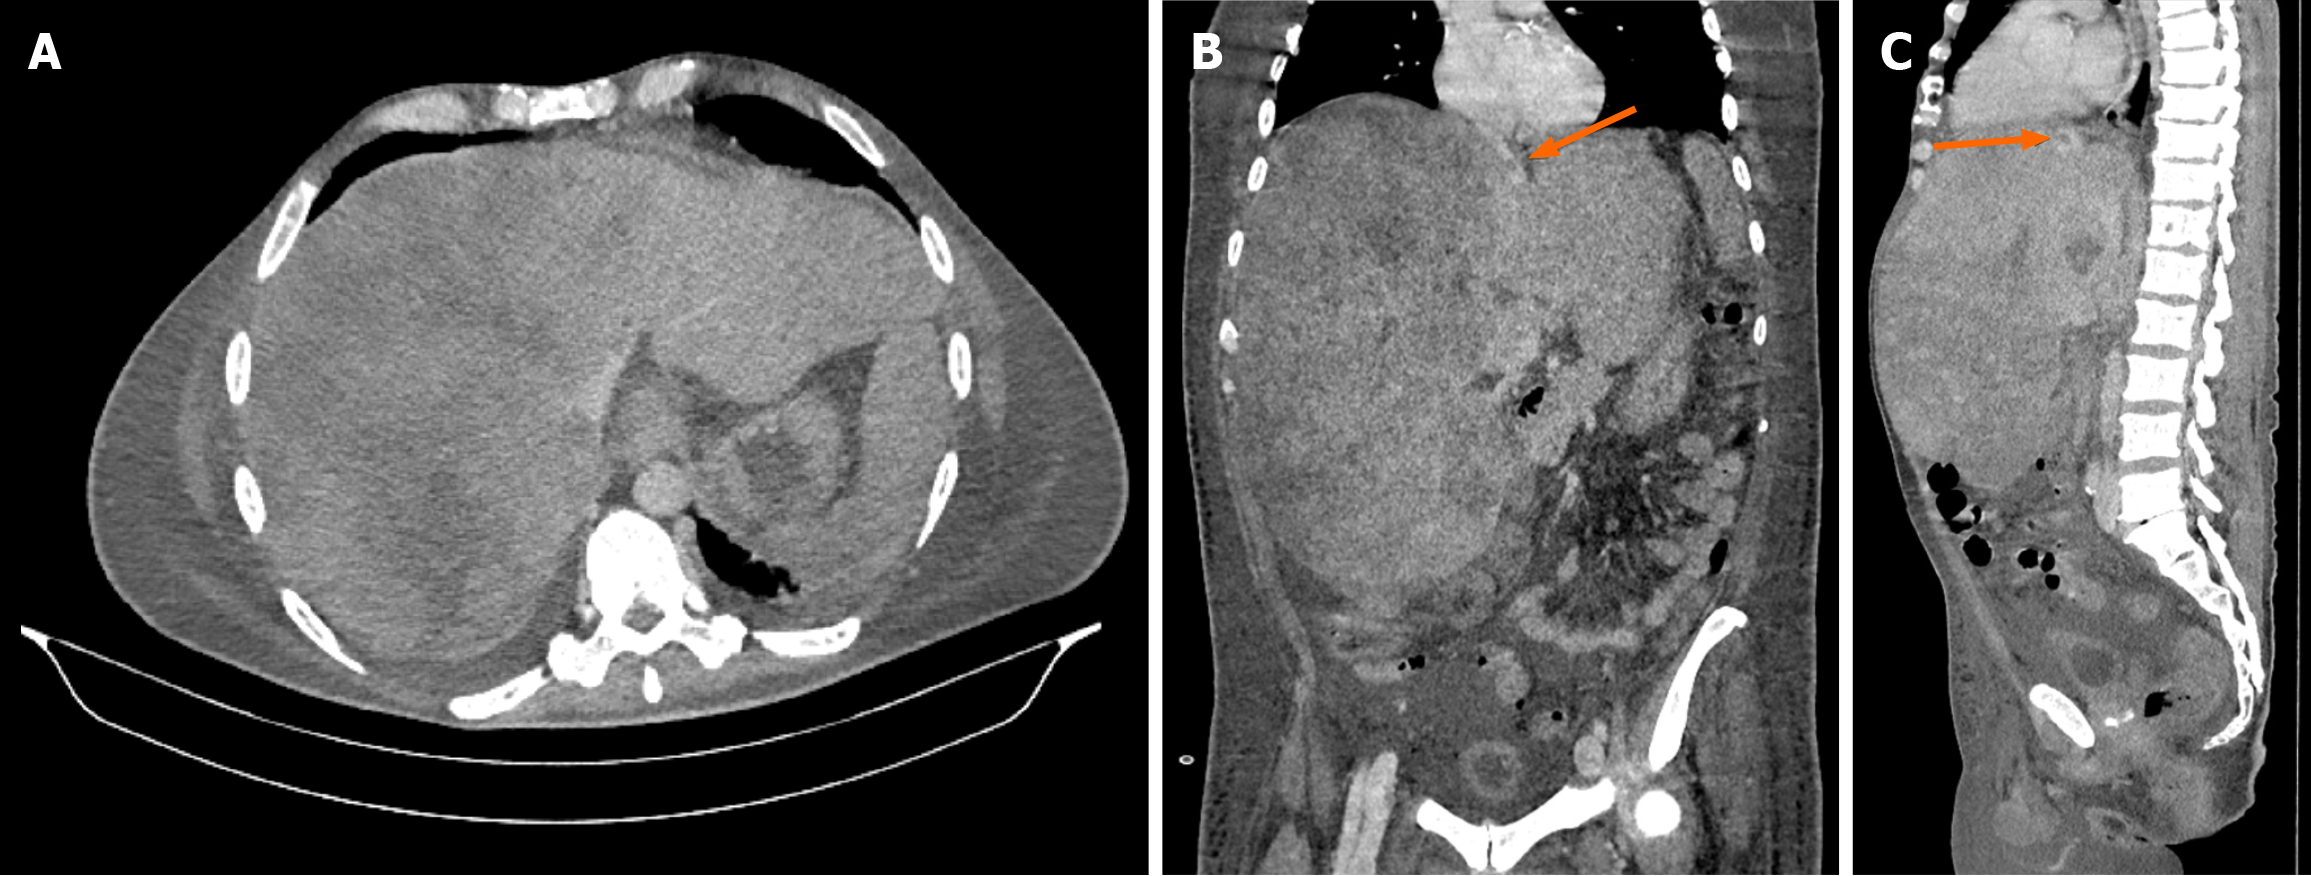

Figure 1 Ultrasound examination.

A: Marked hepatomegaly with multiple hypervascular lesions in the liver; B: Sagittal section showing hepatomegaly, thrombus in the left hepatic vein (arrow), with absence of the right and middle hepatic veins; C: Sagittal section showing hepatomegaly and thrombus in the left hepatic vein.